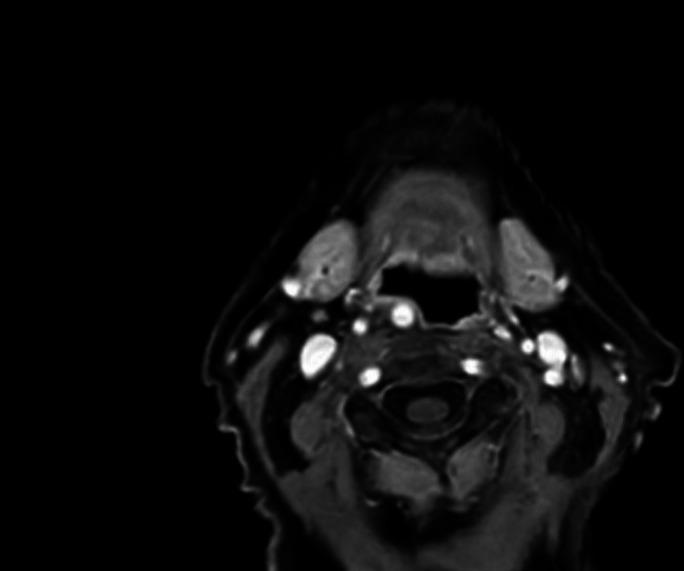

异常颈内动脉导致的吞咽困难:一例报告

Dysphagia from an aberrant internal carotid artery: a case report.

We present a case of dysphagia caused by an aberrant internal carotid artery (ICA). By reporting this rare occurrence, we hope to highlight the anomaly as a differential in cases of persistent, progressive dysphagia.

我们报告一例由异常颈内动脉(ICA)引起的吞咽困难病例。通过报告这一罕见病例,我们希望强调该异常情况可作为持续性、进行性吞咽困难病例的鉴别诊断之一。